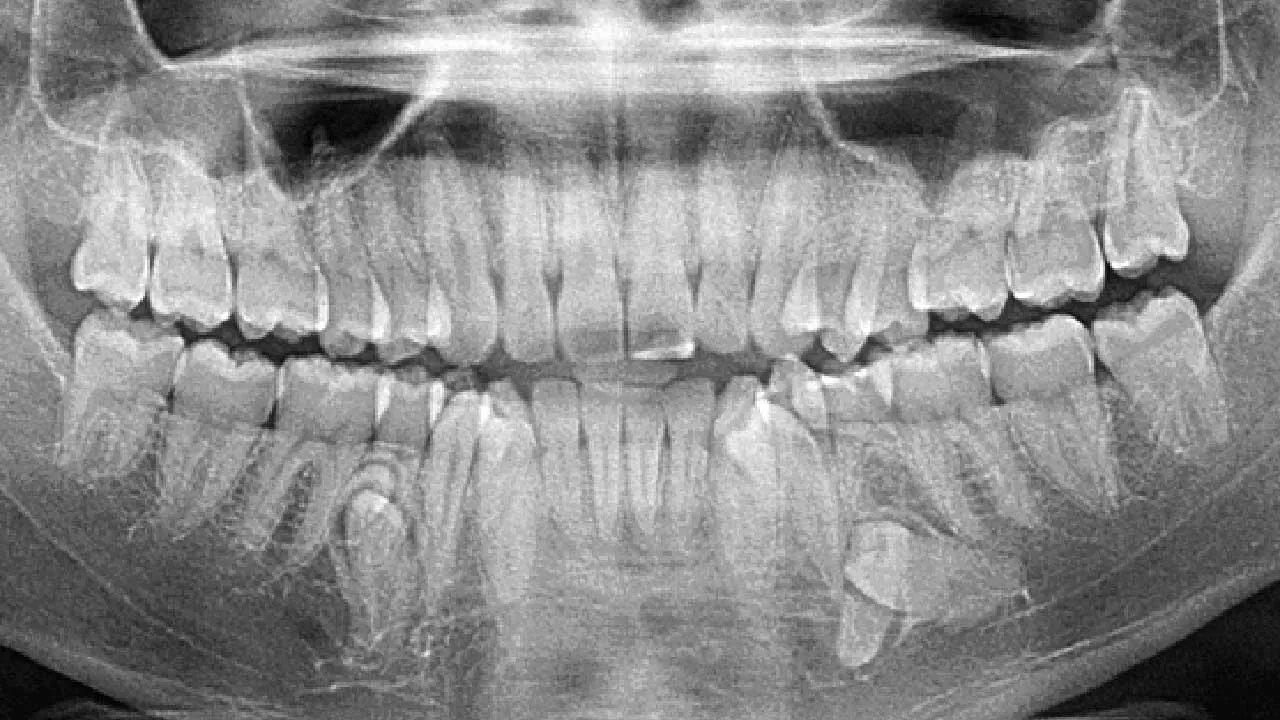

ભારતમાં એક અનોખો વિશ્વ રેકોર્ડ બન્યો છે. કલ્પના બાલન નામની 26 વર્ષની મહિલાના મોઢામાં કુલ 38 દાંત છે, જે સામાન્ય માણસ કરતાં 6 વધુ છે. આ કારણે તેમનું નામ Guinness World Records માં નોંધાયું છે. કોઇ વ્યક્તિના મોઢામાં વધારે દાંત હોય તો શું તે પડાવી દેવા જોઇએ કે રાખવામાં કોઇ વાંધો નથી.

સામાન્ય રીતે એક યુવાન વ્યક્તિના મોઢામાં 32 દાંત હોય છે. પરંતુ કલ્પના બાલનના મોઢામાં 4 વધારાના દાંત નીચેના જડબામાં અને 2 વધારાના દાંત ઉપરના જડબામાં છે. તેમના વધારાના દાંત કિશોરાવસ્થામાં ધીમે-ધીમે ઉગવા લાગ્યા હતા. તેમને ખાસ પીડા તો નથી, પરંતુ ખોરાક ખાતી વખતે ઘણીવાર ખોરાક દાંત વચ્ચે ફસાઈ જાય છે.

આ સ્થિતિને Hyperdontia અથવા supernumerary teeth કહેવામાં છે. આમાં સામાન્ય કરતાં વધુ દાંત વિકસે છે. વિશ્વના લગભગ 3–4% લોકોમાં આ સમસ્યા જોવા મળે છે.